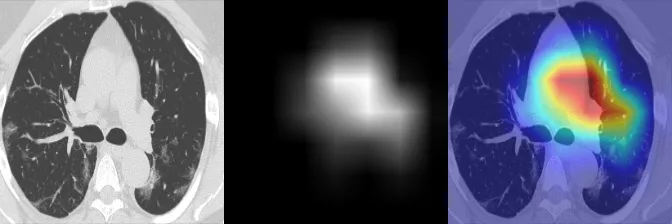

GradCAM visualization

EigenCAM visualization

HiResCAM visualization